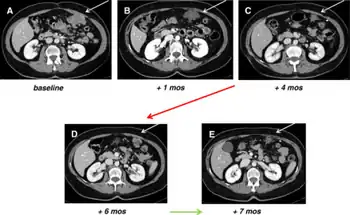

a,b,c) Baseline, after 1 and 4 months of sunitinib-decrease in tumor size d)after 2 months sunitinib interruption e) response after restoring sunitinib